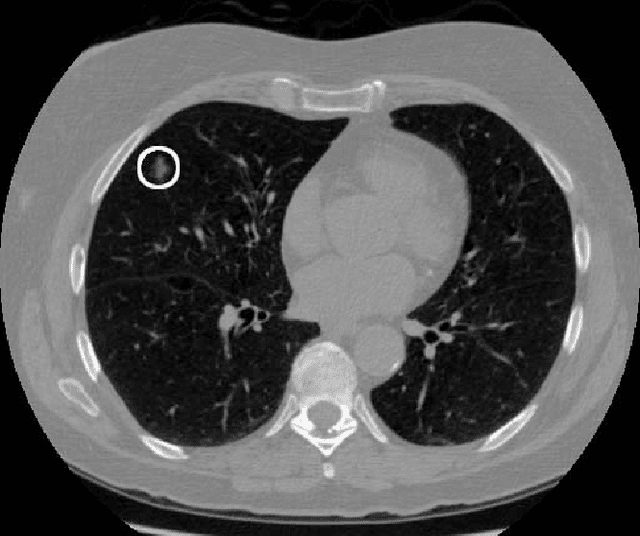

We present a deep learning framework for computer-aided lung cancer diagnosis. Our multi-stage framework detects nodules in 3D lung CAT scans, determines if each nodule is malignant, and finally assigns a cancer probability based on these results. We discuss the challenges and advantages of our framework. In the Kaggle Data Science Bowl 2017, our framework ranked 41st out of 1972 teams.